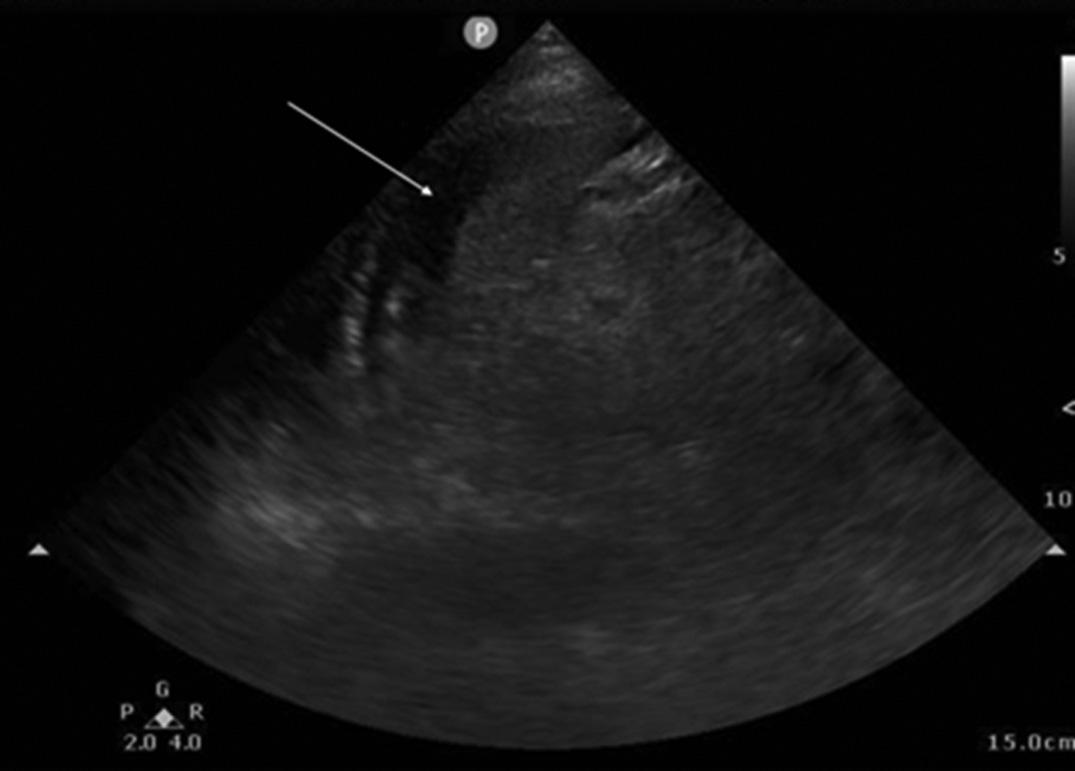

suspicionremainshighforthecondition,acontrast esophagramisthepreferred diagnosticmodality.Barium shouldbeavoidedduetothepossibledevelopmentof mediastinitisifanesophagealleakispresent;instead,watersolublecontrastshouldbeused.1 Althoughnotcommonly includedinthestandarddiagnosisofBoerhaavesyndrome, bedsidepoint-of-careultrasoundhasbeenusedinspecific cases.Findingsonultrasoundincludethepresenceoffree fluid intheupperquadrantsoftheabdomenandairwithinthe pericardiumblockingthenormalvisualizationof cardiacwindows.10